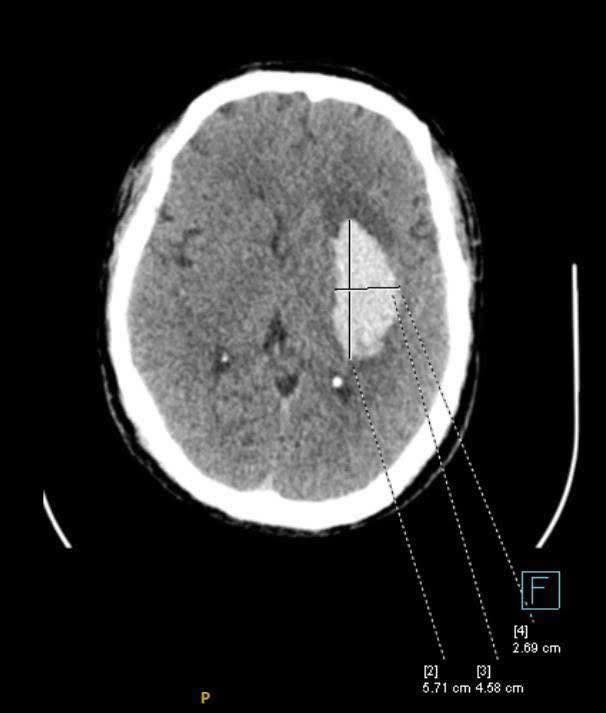

Ổ tổn thương não do đột quỵ.

Khi huyết áp tăng vọt, mạch máu não có thể vỡ, gây liệt nửa người hoặc tử vong. Áp lực cao kéo dài cũng làm tổn thương lớp nội mạc mạch máu, khiến mảng xơ vữa bong ra, gây tắc nghẽn động mạch vành, hậu quả là cơn nhồi máu cơ tim cấp. Trái tim phải làm việc quá sức, phì đại dần và cuối cùng suy yếu: theo Framingham Heart Study, tăng huyết áp chiếm tới 75% nguyên nhân suy tim ở người cao tuổi.